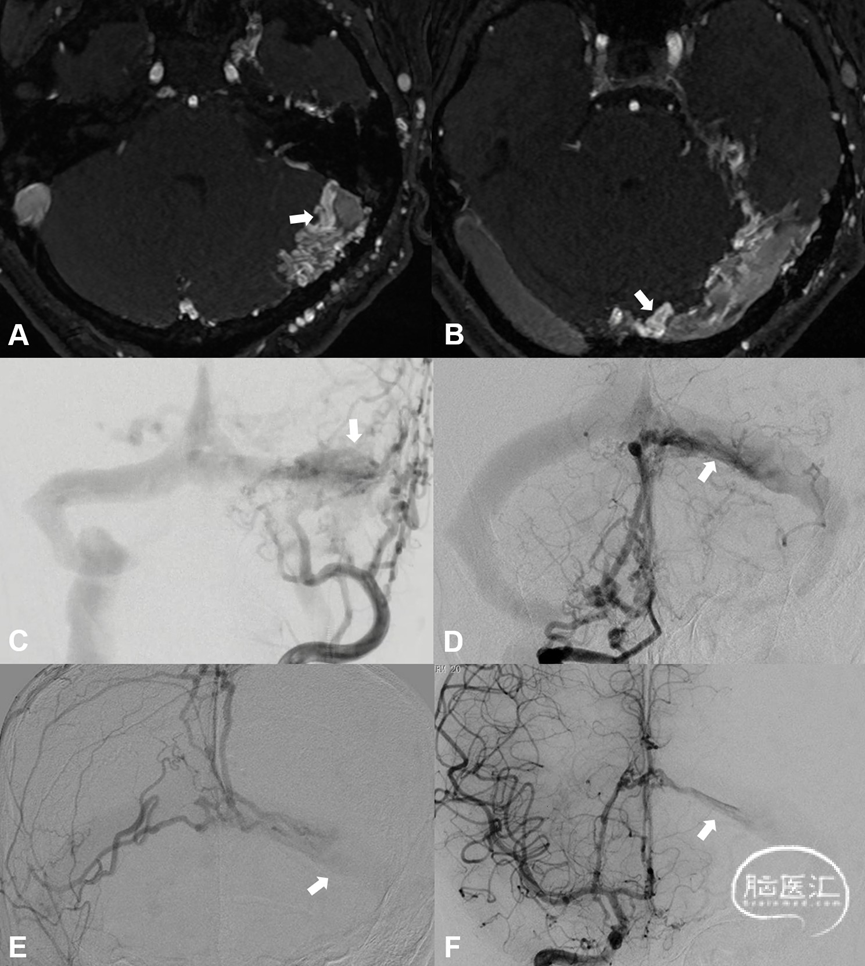

1.静脉窦型硬脑膜动静脉瘘(dural sinus type DAVF, DS-DAVF),以下简称窦型DAVF,即动-静脉移行起自硬膜固有静脉,主要通过硬膜血管汇集区(shunted pouch, SP)向静脉窦引流,软膜静脉可通过静脉窦逆流间接显影。影像学表现为静脉窦早于软膜静脉显影(图2)。

图2. 窦型DAVF的血管构筑与硬膜血管汇集区。侧窦区窦型DAVF,起自硬膜固有静脉系统向横-乙交界区汇聚(A-C)

2.桥静脉型硬脑膜动静脉瘘(bridging vein type DAVF, BV-DAVF),即动-静脉移行起自硬膜固有静脉,经桥静脉硬膜内段向软膜静脉逆流。由于桥静脉向静脉窦直接引流受阻,动静脉瘘无法直接进入静脉窦,而通过侧枝吻合进入邻近静脉窦。影像学表现为桥静脉-软膜静脉早显,并早于静脉窦显影(图3)。

图3. 桥静脉型DAVF的血管构筑。侧窦区桥静脉型DAVF的起点位于桥静脉硬膜内段,由MMA(黑箭)供血,向软膜静脉逆流(A)。同侧乙状窦(双白箭)晚于桥静脉-软膜静脉间接显影(B)。脑静脉窦期显示静脉窦血流通畅,侧裂浅静脉回流被DAVF竞争性抑制(C)

3.板障-导静脉型硬脑膜动静脉瘘(diploic-emissary vein type DAVF, DEV-DAVF),即动-静脉移行起自骨内的板障静脉或穿骨的导静脉,向静脉窦或浅表静脉系统引流。影像学表现为骨内静脉结构早显,并早于静脉窦显影(图4)。

图4. 骨内静脉系统与板障-导静脉型DAVF。板障-导静脉型DAVF,骨内的初级静脉(A白箭)汇聚至板障静脉SP(B双白箭),经蝶顶窦-海绵窦向眼静脉侧裂浅、深静脉逆流(C)。